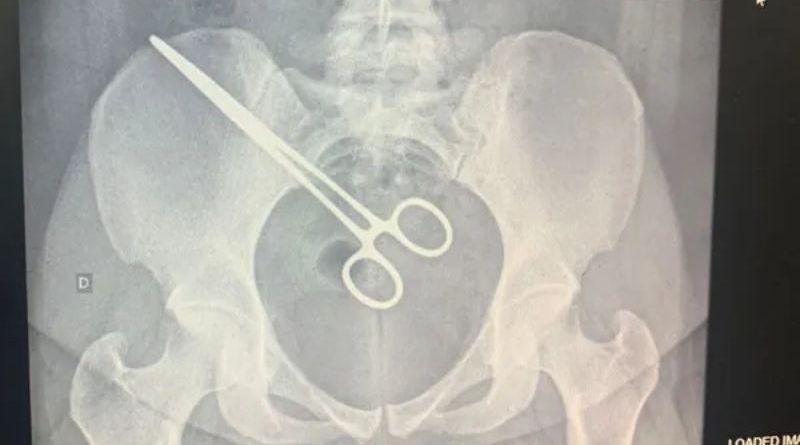

A mulher de 27 anos que passou mais de dois meses com uma pinça cirúrgica dentro do corpo descobriu que o objeto estava na região pélvica ao visitar o marido no Centro de Detenção Provisória (CDP) de São José do Rio Preto (SP).

Após o episódio no CDP, a paciente foi até a Santa Casa, onde fizeram um exame de raio X e constataram que a pinça estava dentro dela. A mulher foi internada novamente no hospital, na segunda-feira, para cirurgia de retirada do instrumento.